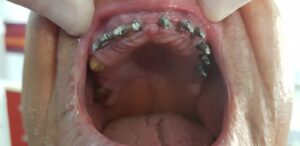

10 implanturi dentare bacau 8 zile (7)